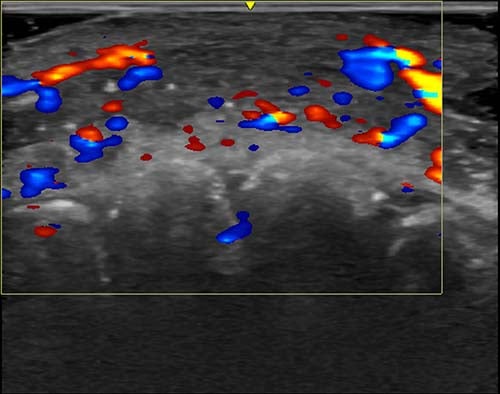

Clinics are now being advised to carry out ultrasounds before injecting dermal fillers to see where the vessels are located.

In just under half of cases, ultrasound scans showed absent flow to blood vessels that connect superficial to deep arteries in the face. In over a third of cases, flow was absent in major blood vessels.

To treat filler-related complications, an enzyme called hyaluronidase is injected to break down the hyaluronic acid filler material. Ultrasound also helps guide clinicians to the area that needs treating.

“If injectors are not guided by ultrasound, they treat based on where the clinical findings are and inject blindly,” Dr Sigrist added.

“But if we can see the ultrasound finding, we can target the exact place where the occlusion occurs. Rather than flooding the area with hyaluronidase, we can do guided injections that use less hyaluronidase and provide better treatment results.”

Ultrasound is also a useful tool for guiding the filler injections themselves and can help with precision, so that less is needed and complications are less likely from the start, she explained.